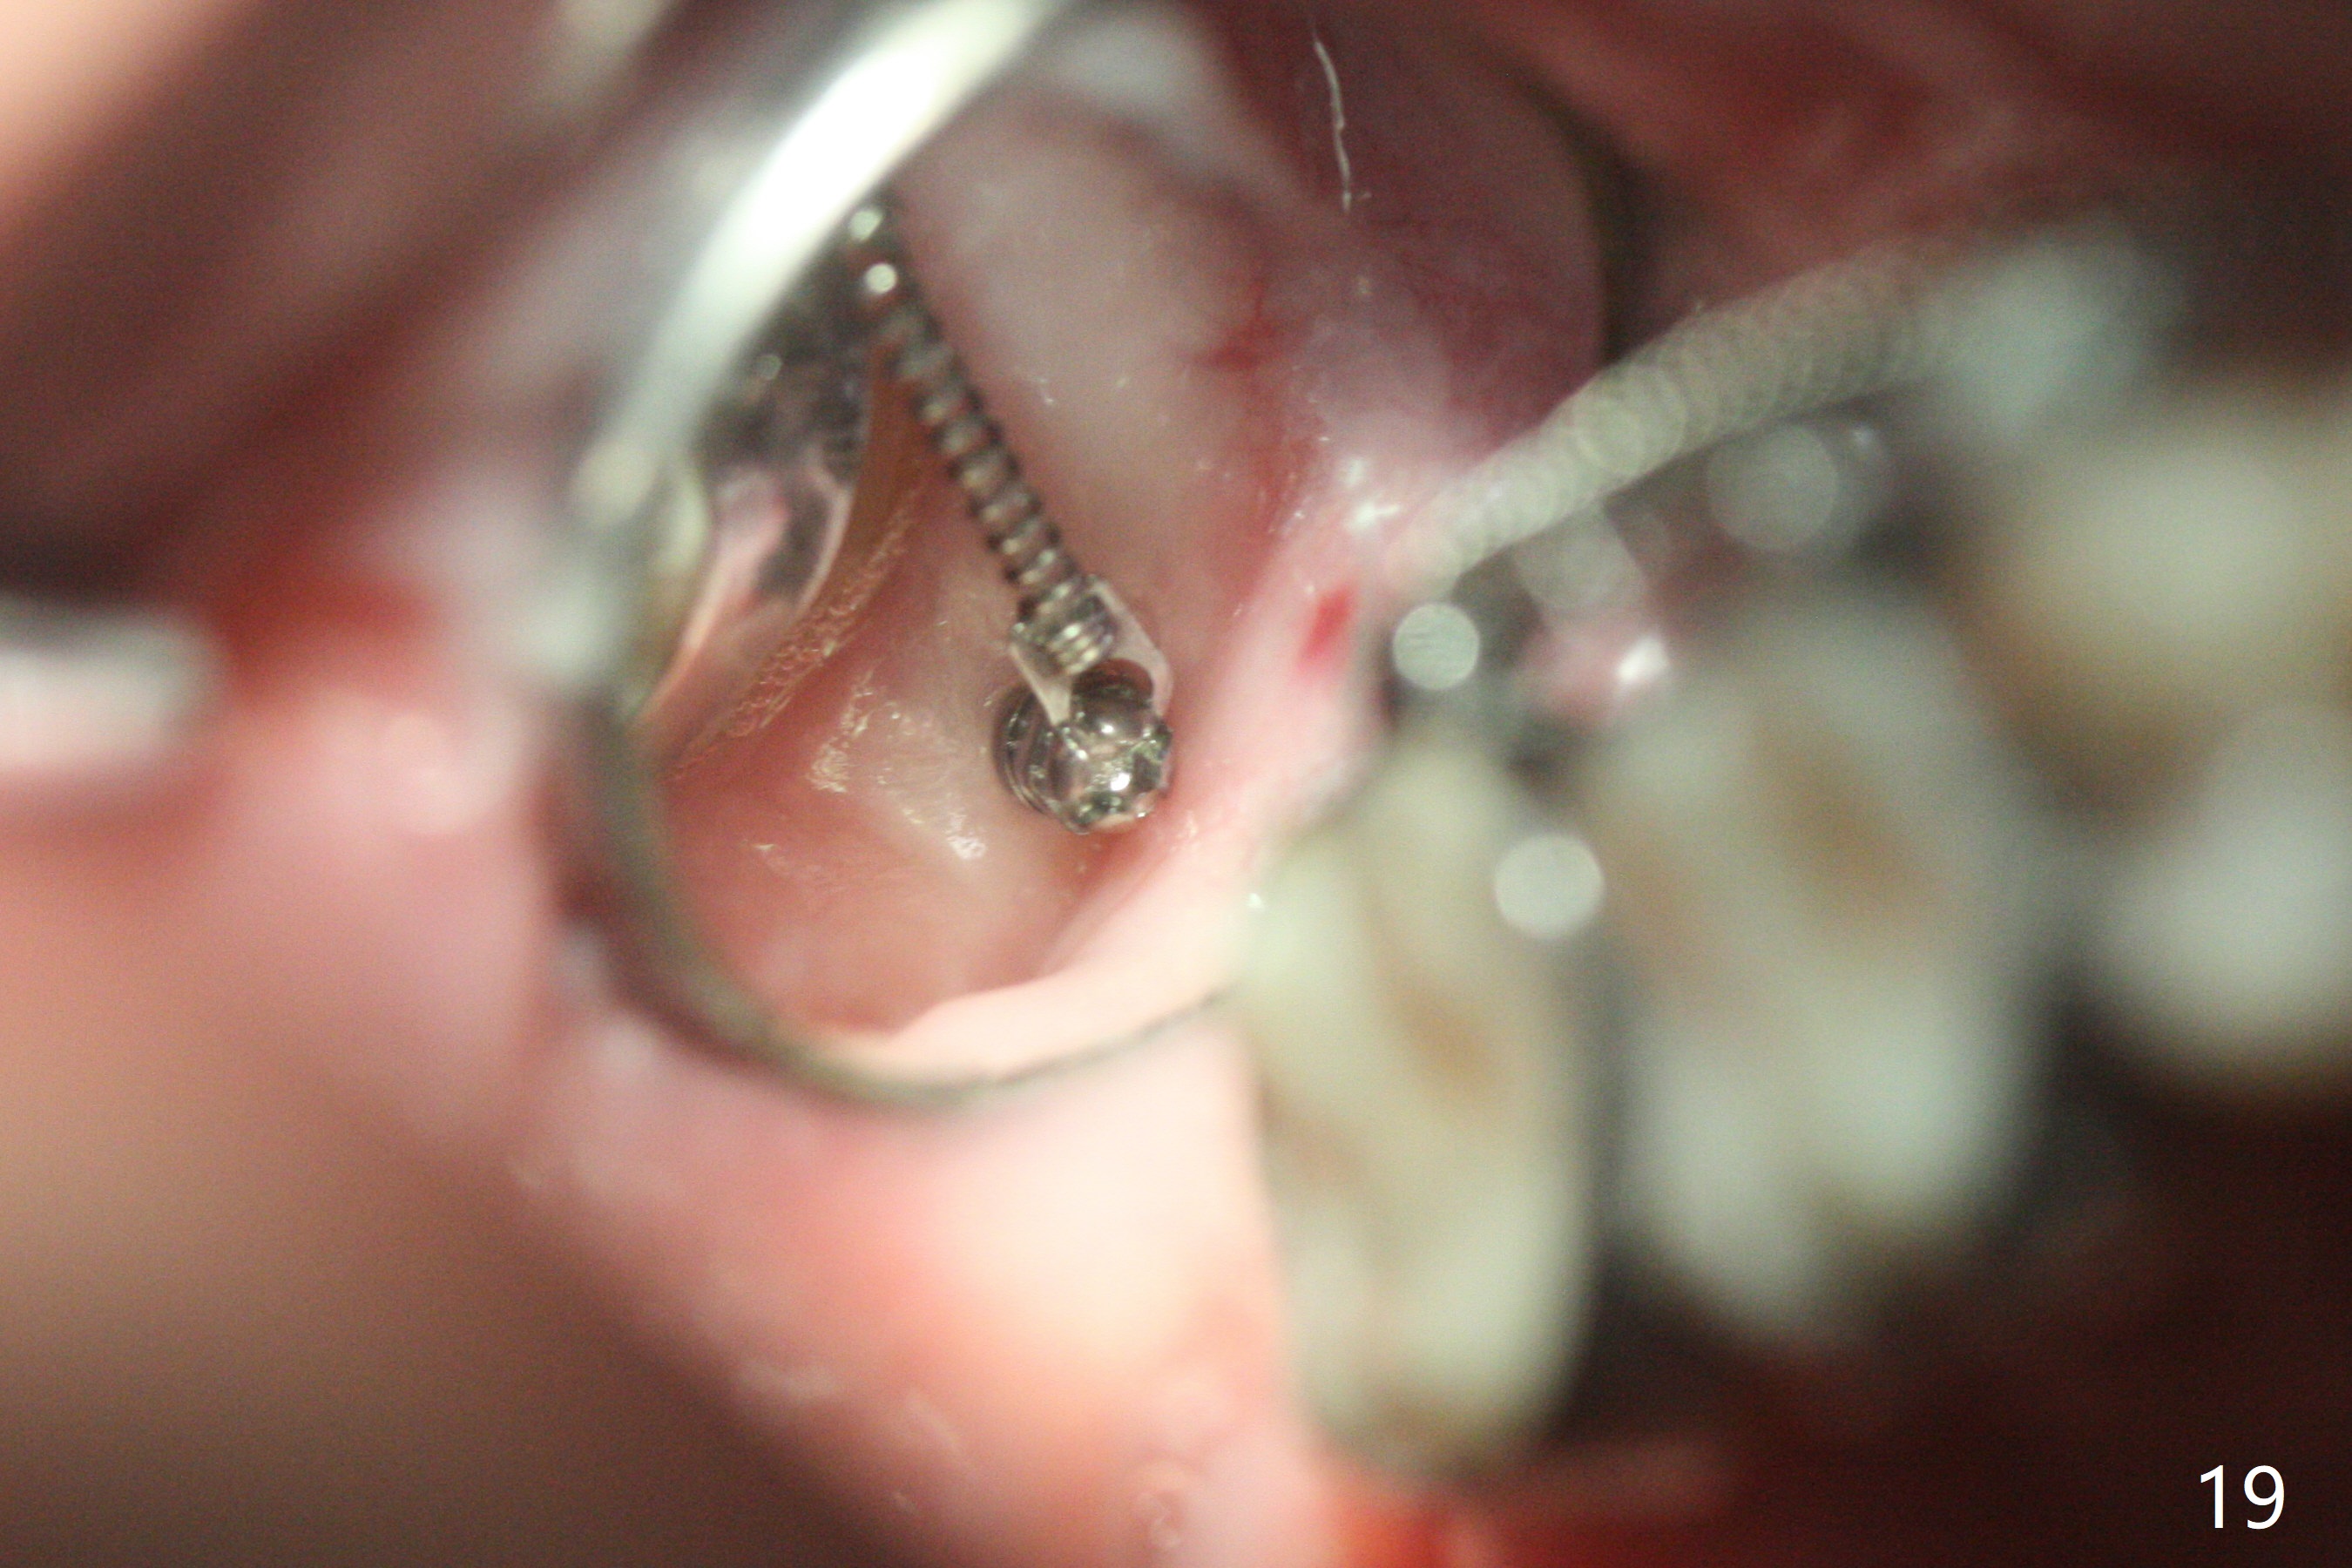

A 40-year-old man requests orthodontics after #17 and 32 extraction. UL5 is missing (Fig.1), while the upper midline deviates to the left (Fig.2 arrow) with crowding between UL2 and 3 (Fig.3). The main goal is to retract UL5 distal and move the upper midline to the right to alleviate UL anterior crowding. Implant will be not needed. To monitor potential root resorption associated with tooth movement, preop PAs are taken (Fig.4-7). The space for an implant at UR5 is narrow. UR4 needs to be distalized using UR7 or a miniimplant distal to UR7 as an anchor (Fig.8). UR4 and 3 will be repositioned to establish Class I occlusion (Fig.9). The space gained by UR4 distalization may be enough to correct the upper midline deviation and UL3 malposition (Fig.10). Brackets will be placed in the lower arch in spite of the normal alignment (Fig.11). UL2 and 3 brackets are unable to be engaged to 14 niti wire (Fig.12). Next visit try to engage UL2 bracket. If not, save the old wire for possible future reuse. Closed spring is placed with 18 ss wire <3 months post banding (coronavirus). Three weeks post closed spring between UR4-7, UR3,4 are being distalized (Fig.13). Distalization of UR4 is not much in 5.5 months (Fig.14,15). It seems necessary to use a miniimplant distal to UR7 as an anchor (Fig.16 white circle), place a long hook mesial to UL4 (more or less root movement instead of tilt) and place the same closed spring between the anchor and hook. In spite of the fact that UR4 seems to have been completely distalized and that UR2 is being distalized 8 months post banding (Fig.18), a 8 mm long mini-implant is placed in the maxillary tuberosity with minimal local anesthetic (Fig.17,19). A longer closed spring (18 mm) is placed between the implant and UR3 hook (Fig.20). Next appointment a lingual button will be placed at UR4 for rotation, while a post hook mesial to UR3 for torque. UR3 distalizes with the help of UR mini-implant, which is unfortunately loose. Next visit place lingual button at UR4 (Fig.21 arrow) to distalize the lingual cusp. Crimpable power hook is placed mesial to UR2 for distalization (for root torque, Fig.22). If it works, remove the wire and reposition the hook for UR1 next visit. UR2 is distalized in one appointment (~ 1 month, Fig.23, as compared to Fig.22). With lingual button at UR4, rotation seems to have been corrected shortly (Fig.24 arrow).